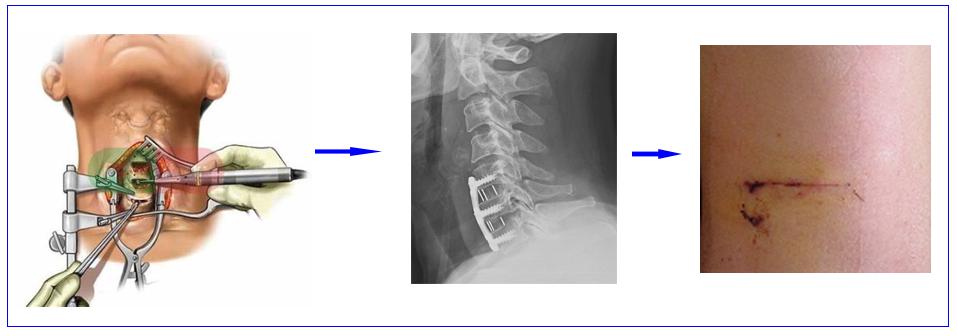

1、颈椎前路融合手术: 是治疗颈椎病的金标准,不仅创伤非常小、且疗效确切、治疗彻底、安全性也非常高,适合大部分神经根型颈椎病和脊髓型颈椎病患者。颈椎前路融合手术通过去除突出的椎间盘、增生的骨赘、和肥厚的后纵韧带,以达到解除神经压迫的目的;同时还能通过植骨融合解决椎体间的不稳。一般情况术后第1天即可下地,术后3天左右即可回家。